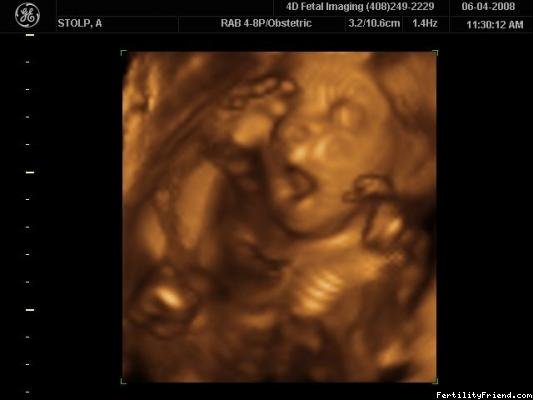

Obrázky z 3D ultrazvuku - 29. týden těhotenství

Obrázky z 3D ultrazvuku - 30. týden těhotenství